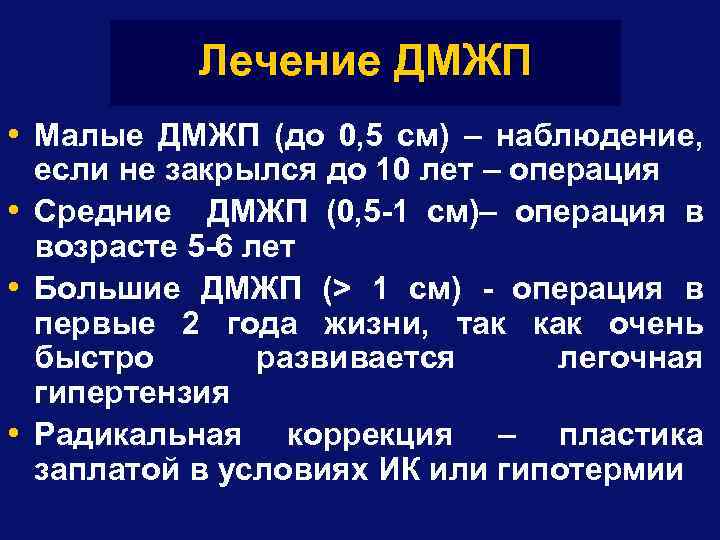

Лечение ДМЖП • Малые ДМЖП (до 0, 5 см) – наблюдение, если не закрылся до 10 лет – операция • Средние ДМЖП (0, 5 -1 см)– операция в возрасте 5 -6 лет • Большие ДМЖП (> 1 см) - операция в первые 2 года жизни, так как очень быстро развивается легочная гипертензия • Радикальная коррекция – пластика заплатой в условиях ИК или гипотермии